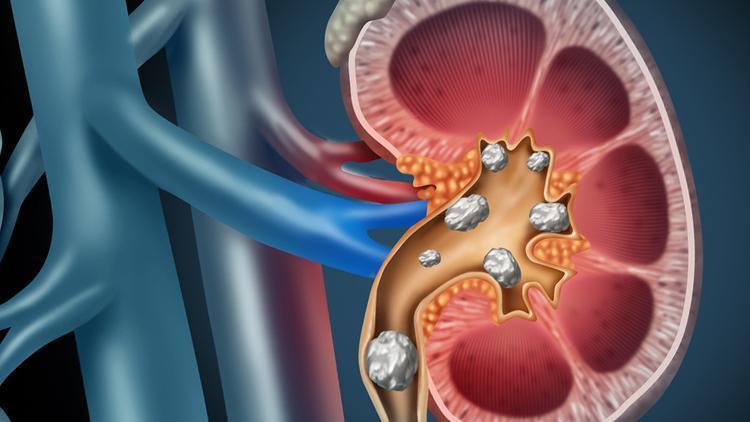

Bu hatalar böbrek taşı yapıyor! Korunmak için doğal besinlerin gücünden faydalanın

Gece saatlerinde şiddetli sancılarla uykudan uyandıran böbrek taşı sorunu kimi zaman hayatı kabusa çeviriyor. Bu sorunla başa çıkan kimselerin ise denemediği yol kalmıyor. Peki, böbrek taşının oluşmaması için neler yapabiliriz? Böbrek hastalıklarının tedavisine yardımcı olan ve böbreklere iyi gelen besinler neler? İşte merak edilen sorulara dair uzmanlardan öneriler…

Halk arasında ‘idrar yollarından kum dökme’ olarak bilinen bu hastalık erkeklerde kadınlara göre iki üç kat daha fazla görülüyor. Üroloji Uzmanı Doç. Dr. Hakan Özveri, böbrek taşının en çok yetersiz sıvı alımından kaynaklandığını belirterek “Bununla birlikte, son yıllarda sağlıksız beslenme, aşırı tuz tüketimi ve yüksek proteinli diyetler yapılması da idrardaki mineral yoğunluğunun, böbreğin eritebileceğinden fazla miktarda olmasına ve böbrek taşları oluşumuna neden oluyor” diyor. Taşa bağlı bir idrar yolu tıkanıklığının, böbreklerde hızla ilerleyen bir enfeksiyona zemin hazırlayabildiğini, hastalarda ateş, üşüme ve titremenin de görülebildiğini belirten Doç. Dr. Hakan Özveri, böbrek taşı tedavi edilmediği takdirde ileride böbrek kaybına bile yol açabildiğini söylüyor; böbrek taşından korunmanın 7 etkili yolunu anlatıyor ve önemli uyarılarda bulunuyor.